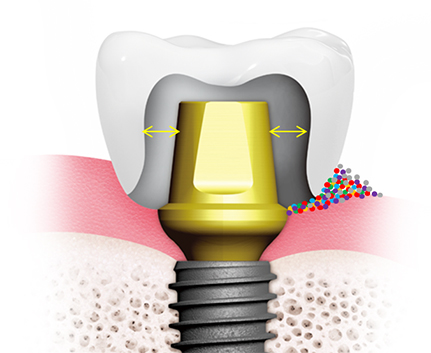

서울하나치과의 네비게이션 임플란트는 디지털 정밀진단과

가상 시뮬레이션을 통해

오차없이 최적의 식립장소에 정확하게 식립합니다.

오스템 임플란트

덴티스 임플란트

신흥 에버티스 임플란트

| PFM 보철물 | VS | 지르코니아 보철물 |

|---|---|---|

| 겉 - 도자기, 속 - 금속 | 소재 | 지르코니아 블록 |

| 치아와 잇몸 라인에 검은 띠가 보임 | 심미성 | 자연치아와 유사하며, 검은 띠가 생기지 않음 |

| 속은 단단하나 겉이 약함 | 강도 | 금이나 세라믹보다 강하고 단단함 |

| 있음 | 중금속 노출 가능성 |

없음 |